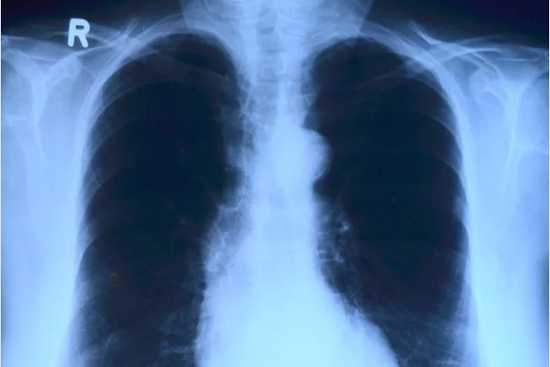

º¸Àº±ºº¸°Ç¼Ò, ¼±º°Áø·á¼Ò ³» X-·¹ÀÌ ÃÔ¿µ±â ¿î¿ë

À̵¿Çü X-ray¼³Ä¡·Î ¼±º°Áø·á ±â´É °­È­, Æó·Å°Ë»ç ½Å¼Ó È®ÀÎ

º¸Àº±º º¸°Ç¼Ò(¼ÒÀå ÀÌ¿µ¼ø)´Â Äڷγª19 È®ÁøÈ¯ÀÚ°¡ Áö¼ÓÀûÀ¸·Î ¹ß»ý¿¡ µû¸¥ ±º¹ÎµéÀÇ ºÒ¾È°¨À» ÇØ¼ÒÇϱâ À§ÇØ ¼±º°Áø·á¼Ò¿¡ À̵¿Çü X-ray¸¦ ¼³Ä¡ÇØ ¼±º°Áø·á ±â´ÉÀ» °­È­ÇÑ´Ù°í 26ÀÏ ¹àÇû´Ù.

ÀÌ¿¡ µû¶ó Äڷγª19 ÀÇ½É È¯ÀÚ ¹æ¹® ½Ã º¸°Ç¼Ò ¾ÈÀ¸·Î À̵¿ÇÏÁö ¾Ê°í, ¿Á¿Ü¿¡ ÀÖ´Â ¼±º°Áø·á¼Ò¿¡¼­ Æó·Å Áø´Ü °Ë»ç¸¦ ½Å¼ÓÇÏ°Ô ÃÔ¿µÇÒ ¼ö ÀÖ°Ô µÆ´Ù.

±º º¸°Ç¼Ò °ü°èÀÚ´Â "º¸°Ç¼Ò¸¦ ÀÌ¿ëÇÏ´Â Áö¿ªÁֹΰú °¨¿° ÀǽÉÀÚ¿ÍÀÇ Á¢ÃËÀ» ¹æÁöÇØ Áö¿ª ³» °¨¿°À» Â÷´ÜÇϰí Äڷγª19ÀÇ Á¶±â Áø´ÜÀÌ °¡´ÉÇÏ°Ô µÆ´Ù"¸ç "ÇöÀç Áö¿ª ³» ÀüÆÄ¸¦ Â÷´ÜÇϱâ À§ÇØ ¹æ¿ª°ú ¿¹¹æ¿¡ ÃÖ¼±À» ´ÙÇϰí ÀÖ´Ù"°í ¸»Çß´Ù.